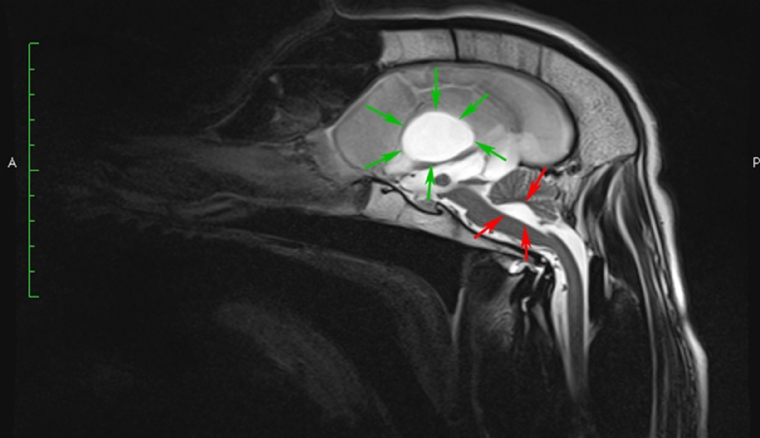

Mercredi 30 Mai 2018 Animaux de compagniePhoto n° 1 : Coupes sagittales en pondération T2. Dilatation majeure des ventricules latéraux avec la présence d'un diverticule du troisième ventricule (flèches vertes). Dilatation modérée du quatrième ventricule entraînant une compression du cervelet (flèches rouges).

© Service d'imagerie médicale Oniris